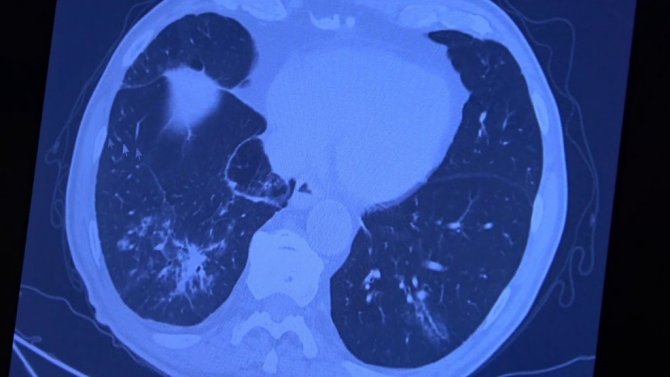

Korona virüs hastalığı genç nüfusta daha fazla görülmeye başlarken Covid-19 aşıları tamamlanan 60 yaş üstü vatandaşlardan bazıları ise korona virüse yakalanmaya devam ediyor. VM Medical Park Samsun Hastanesinde görev yapan Göğüs Hastalıkları Uzmanı Prof. Dr. Şevket Özkaya ise aşının gerçek yaşam sonuçlarını gözler önüne serdi. 2. doz aşıları tamamlanmış fakat Covid-19 servisinde yatan hastaların akciğer tomografilerini inceleyen Prof. Dr. Özkaya, bu kişilerin akciğer tutulumları olduğu halde hastalığı hafif atlattıklarını söyledi.

Bugüne kadar aşının etkilerini hep laboratuvar ortamında antikor üretip üretmemesi ile değerlendirdiklerini belirten Prof. Dr. Özkaya, "Vatandaşlarımız aşılarını olduktan sonra ilk gerçek yaşam sonuçlarını yeni yeni almaya başladık. Gerçekten aşı yaptığımızda antikor oluşturuyor ama bu antikor kişiyi koruyacak mı diye merakla beklediğimiz sorunun cevabını, insanlar 2. doz aşısını olduktan bir ay sonra ortaya çıkmaya başladı. Bu hastalar korona virüsü kaptığında yeni yeni korumaya başladığını anladık. Bir örnek vermem gerekirse, 84 yaşında bir hastamız 2. doz aşısını olduktan sonra eşiyle beraber Covid-19 oluyor. Korona virüsü akciğer tutulumları olduğu halde çok hafif şekilde atlattılar. 65 yaşında başka bir hastamızı göstermek gerekirse, bu hastamız da 2. doz aşısını olmuş ve aradan 1 ay geçtikten sonra antikor da oluşmuş. Bu antikor bu kişiyi koruyacak mı diye gerçek yaşam sonuçlarına baktığımızda, koronanın hastanın akciğerlerine indiği halde çok hafif atlattığını görüyoruz. Eğer bu kişi aşı olmasaydı, hastaneye yatarak daha ağır geçirebilirdi" diye konuştu.

Covid-19 servisinde yatan hastaların yüzde 80'inin gençlerden oluştuğunun altını çizen Prof. Dr. Özkaya, "Artık daha genç hastaların mutant virüsle karşılaştıkları için daha ağır geçirdiği görüyoruz. 60 ve 65 yaş üstünü ise aşıyla sigortaladığımızı düşünüyoruz. Aşının gerçek yaşam sonuçlarının olumlu olduğunu görüyoruz. Aşı olanlar virüse yakalandıkları halde çok hafif veya hastaneye yatmadan atlatıyorlar. Şu an servisimizde yatan hastaların yüzde 80'inini genç hastalar oluşturuyor. Artık 60 yaş üstünde çok fazla hasta görmüyoruz. Örneğin (akciğer filmini gördüğümüz) 40 yaşındaki bir hastamız aşılanmadığı için mutant virüse yakalanmış. Akciğerleri çok kötü durumda ve hastanede yatıyor. 24 yaşında bir genç kızımızda ise ciddi akciğer tutulumları görüyoruz. 49 yaşında bir hastamızı ise maalesef çok ciddi akciğer tutulumu ve neredeyse paramparça bir akciğerle yoğun bakımda takip ediyoruz" şeklinde konuştu.